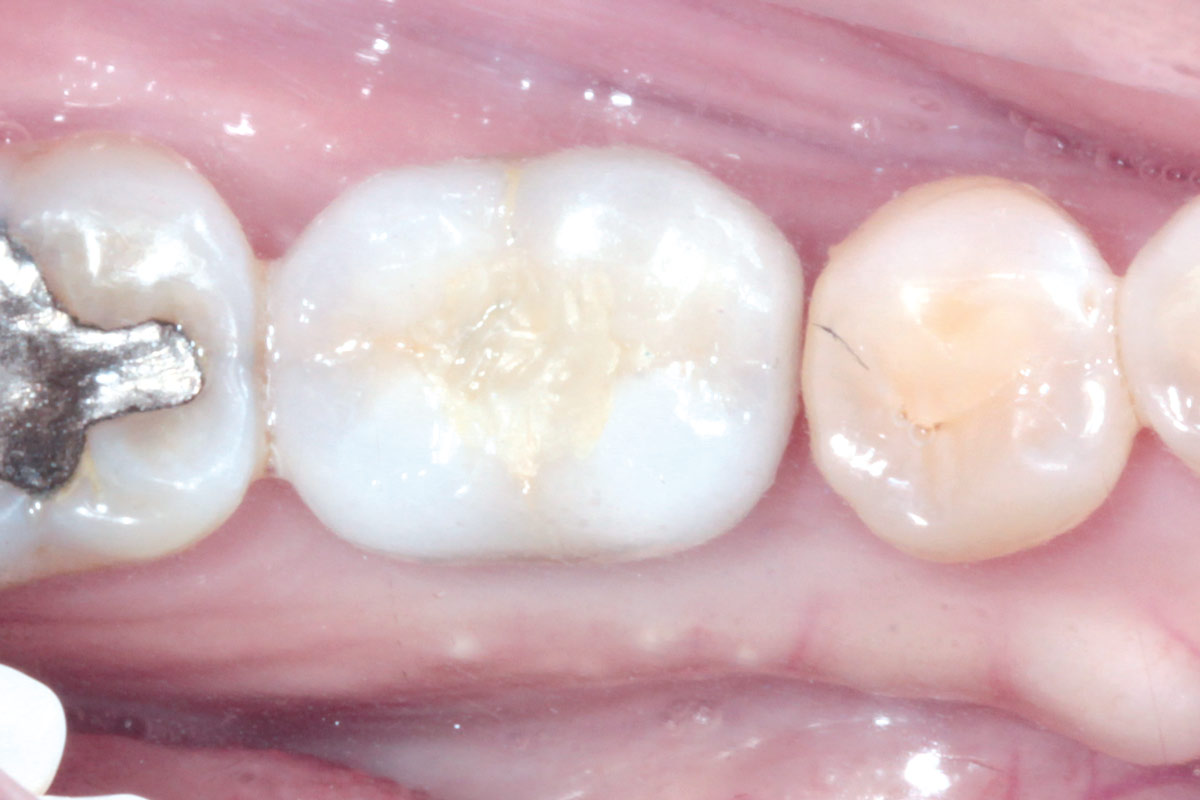

The patient presented with a terminal fracture of the crown tooth number 12